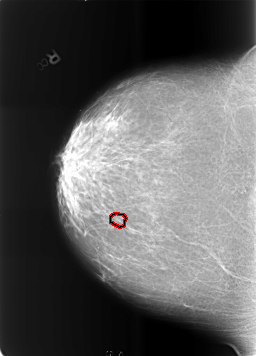

ics_version 1.0 filename B-3465-1 DATE_OF_STUDY 12 5 1998 PATIENT_AGE 67 FILM FILM_TYPE REGULAR DENSITY 2 DATE_DIGITIZED 7 4 1999 DIGITIZER LUMISYS LASER SEQUENCE LEFT_CC LINES 5680 PIXELS_PER_LINE 4176 BITS_PER_PIXEL 12 RESOLUTION 50 NON_OVERLAY LEFT_MLO LINES 5704 PIXELS_PER_LINE 4152 BITS_PER_PIXEL 12 RESOLUTION 50 NON_OVERLAY RIGHT_CC LINES 5696 PIXELS_PER_LINE 4088 BITS_PER_PIXEL 12 RESOLUTION 50 OVERLAY RIGHT_MLO LINES 5712 PIXELS_PER_LINE 4104 BITS_PER_PIXEL 12 RESOLUTION 50 OVERLAY |

FILE: B_3465_1.RIGHT_CC.OVERLAY TOTAL_ABNORMALITIES 1 ABNORMALITY 1 LESION_TYPE CALCIFICATION TYPE PLEOMORPHIC DISTRIBUTION CLUSTERED ASSESSMENT 4 SUBTLETY 2 PATHOLOGY BENIGN TOTAL_OUTLINES 1 BOUNDARY |